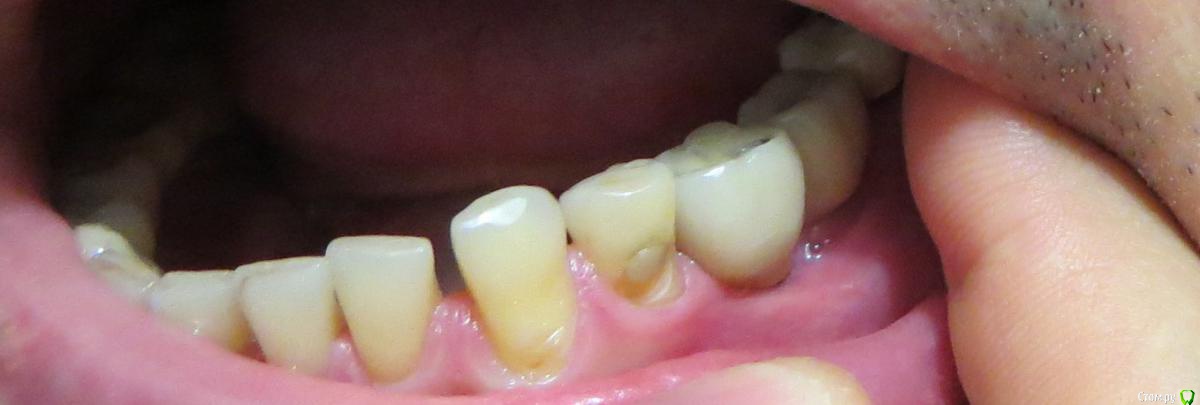

kozloff Опубликовано 23 октября, 2015 Поделиться Опубликовано 23 октября, 2015 (изменено) Сделайте фото этих зубов в полости рта, должны быть видны коронки и десна Изменено 23 октября, 2015 пользователем kozloff 2 Ссылка на комментарий

витаХА Опубликовано 27 октября, 2015 Автор Поделиться Опубликовано 27 октября, 2015 Сделайте фото этих зубов в полости рта, должны быть видны коронки и деснаСделал фото но не знаю насколько качественно получилось. Поэтому дам небольшие пояснения. На снимке эти коронки вторая и третья, если считать справа. У третьей внизу около края десны видно темноё пятно(это видимо светится метал от коронки).Мне вообще кажется что десна не закрывает полностью коронку у этого импланта и край утолщения коронки(это даже видно на фото) находится сильно над десной.Врач который делал протезирование говорит что десна поднимется со временем и обхватит эту коронку. Ссылка на комментарий

kozloff Опубликовано 27 октября, 2015 Поделиться Опубликовано 27 октября, 2015 Нужно лечить перимиплантит.Подсадить десну.Новые коронки с адекватным профилем появления. Ссылка на комментарий